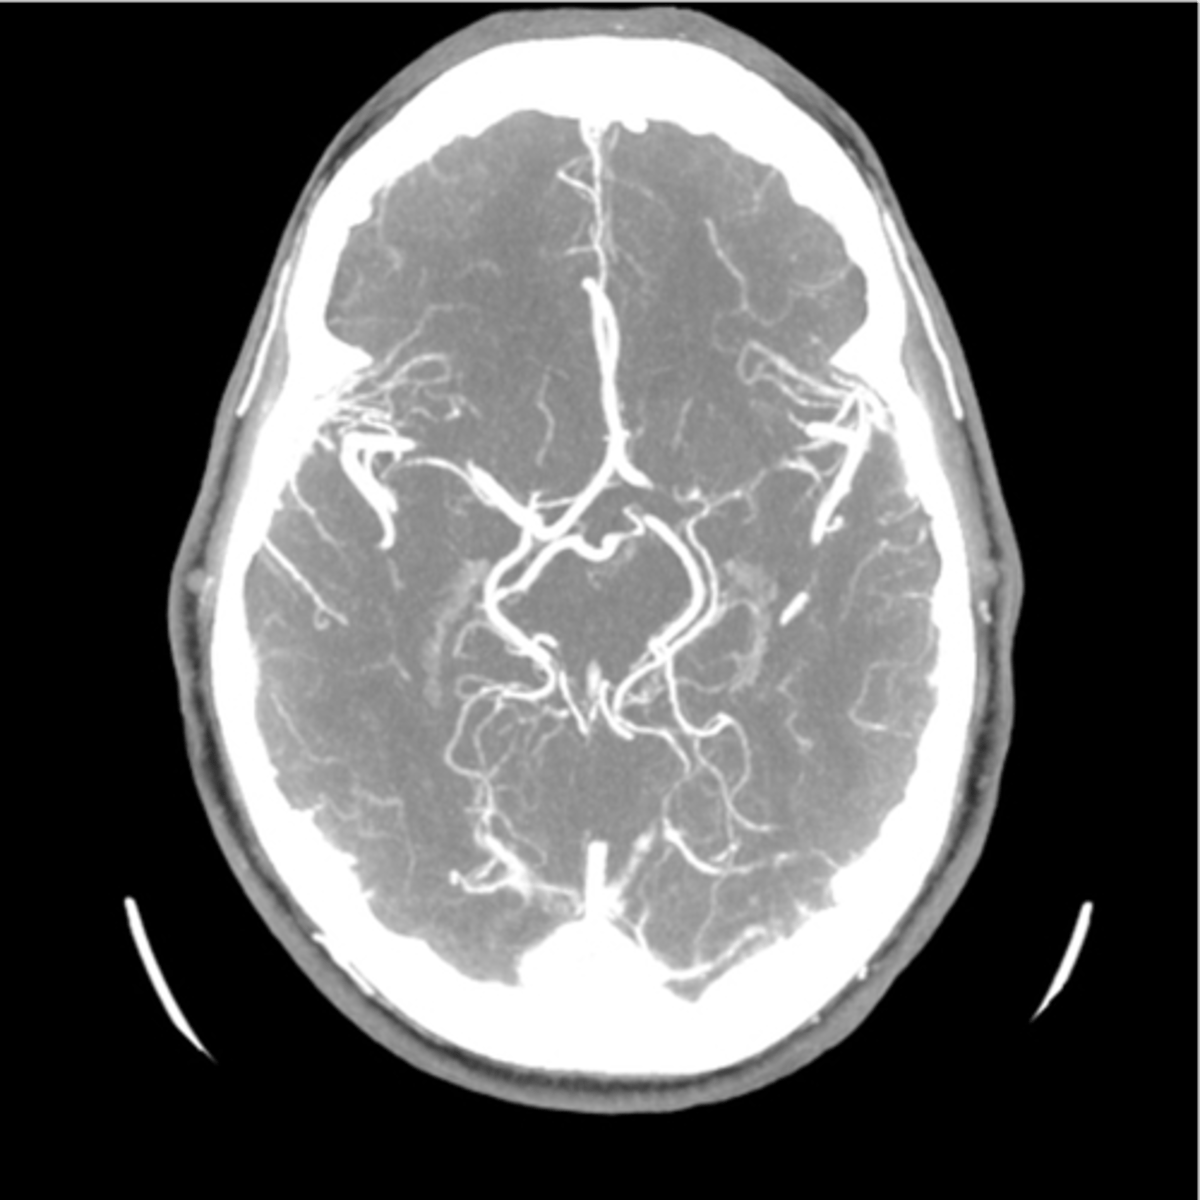

CT w/ IV contrast head can help identify

stroke (ischemic), brain/spine tumors & vascularity, AVM, fractures/spinal stenosis

head MRA evaluates

magnetic resonance angiography